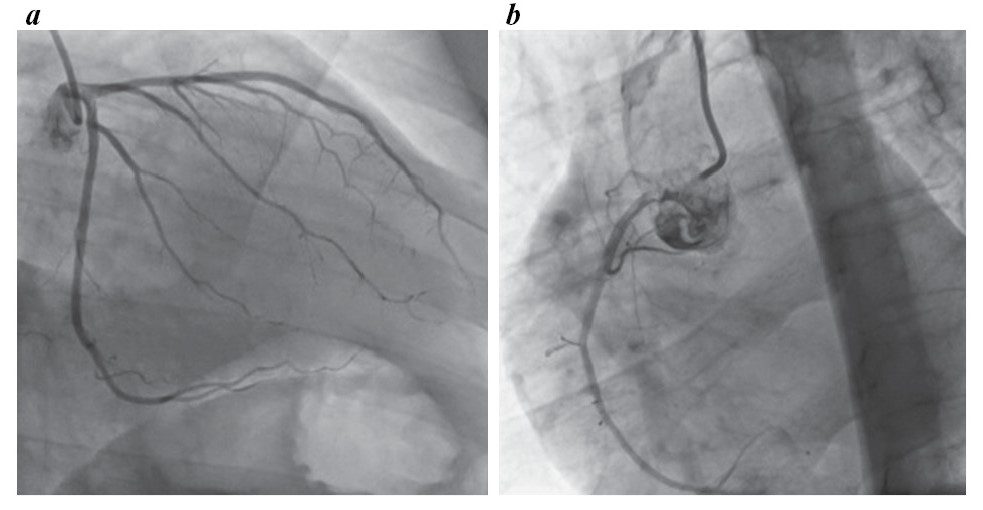

Пациенту проведена коронарография (рис. 6), по данным которой гемодинамически значимых изменений не выявили.

Рис. 6. Коронарография без гемодинамически значимых стенозов.

Fig. 6. Coronary angiography without hemodynamically significant stenoses.